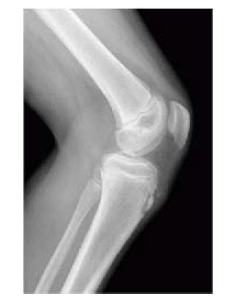

R.L.P, de 14 anos de idade, joga futebol diariamente com colegas de bairro, por ao menos quatro horas diárias. Iniciou, há cerca de um ano, com queixas de dor anterior em ambos os joelhos. Foi realizada a radiografia apresentada.

Com base nesse caso clínico e nos conhecimentos médicos correlatos, julgue os itens a seguir.

O paciente deve ser afastado do esporte por cerca de seis meses.